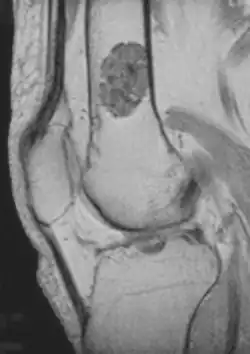

Enchondroma is a type of benign bone tumor that originates from cartilage. The exact etiology of it is not known. An enchondroma most often affects the cartilage that lines the inside of the bones. The bones most often involved with this benign tumor are the miniature long bones of the hands and feet. It may, however, also involve other bones such as the femur, humerus, or tibia. While it may affect an individual at any age, it is most common in adulthood. The occurrence between males and females is equal. It is not very likely that the enchondroma will grow back in the same spot; the rate is less than ten percent.

- X-ray – On plain film, an enchondroma may be found in any bone formed from cartilage. They are lytic lesions that usually contain calcified chondroid matrix (a "rings and arcs" pattern of calcification), except in the phalanges. They may be central, eccentric, expansile or nonexpansile.

Differentiating an enchondroma from a bone infarct on plain film may be difficult. Generally, an enchondroma commonly causes endosteal scalloping while an infarct will not. An infarct usually has a well-defined, sclerotic serpentine border, while an enchondroma will not. When differentiating an enchondroma from a chondrosarcoma, the radiographic image may be equivocal; however, periostitis is not usually seen with an uncomplicated enchondroma.